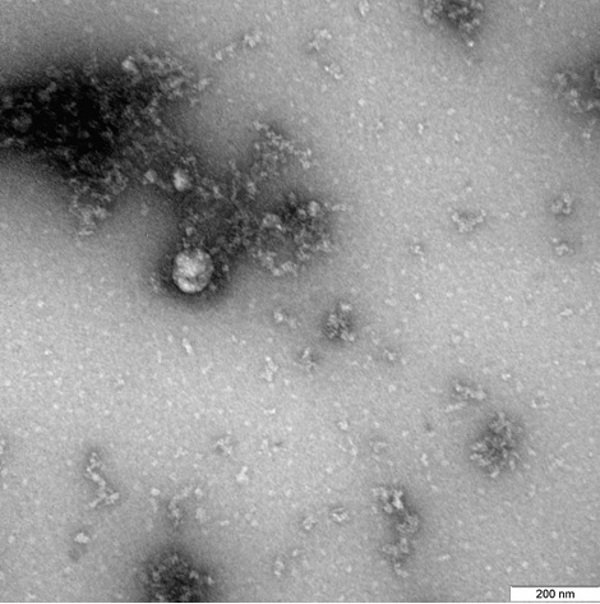

Руски учени първи в света са направили снимка под микроскоп на британския вариант на коронавируса.

Снимката на вируса под микроскоп е получена в рамките на продължаващото изучаване на свойствата на този вариант на новия коронавирус, включително неговите структурни особености и проявлението му в клетъчни култури и експериментални модели с използване на лабораторни животни, се посочва в съобщение на Роспотребнадзор.

В средата на декември във Великобритания беше открита нова мутация на SARS-CoV-2. По-късно стана известно, че той се разпространява с по-висока скорост и може да бъде със 70% по-заразен.